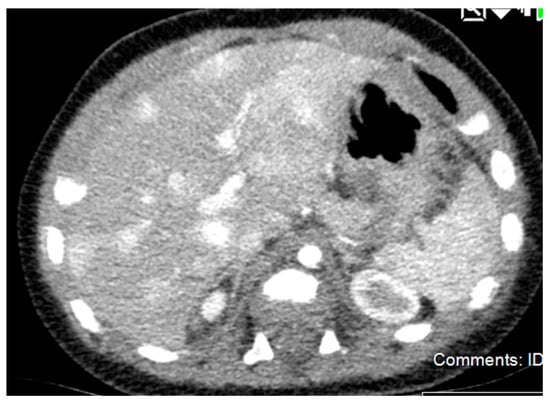

5.2.4. Diagnostic Imaging